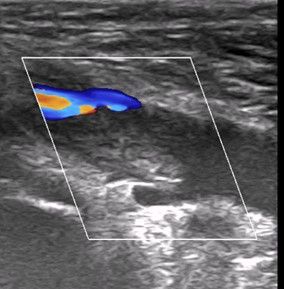

Pacient byl po vyšetření internistou indikován k léčbě apixabanem podávaným týden v dávce 2× 10 g a poté k pokračovací dávce 2× 5 mg. Léčba byla zahájena 27. července, otok vznikl 2. července. Po asi 14 dnech léčby částečně ustoupil, ale pokud pacient nenosí elastickou bandáž, vznikne otok kolem kotníku. Při kontrole v naší ambulanci po 14 dnech léčby má pacient malý otok kolem pravého kotníku. Ostatní všechna známá fyzikální vyšetření zaměřená na hlubokou trombózu jsou negativní, ale sonograficky je stále patrný částečně obturující, spíše hyperechogenní trombus v popliteální žíle, se známkami obtékání, kompresibilním tlakem sondy na 30 % průsvitu žíly (obr. 1a, b). Echokardiografie bez známek plicní hypertenze. Pokračováno v léčbě apixabanem v dávce 5 mg 2× denně, kontrolní laboratorní vyšetření doložila normální renální funkce.

Obr. 1b Dupplexní ultrazvukové vyšetření – stejná poloha sondy, podélný řez s dobře patrným trombem a známkami obtékání, trombus stále vyplňuje většinu lumen.